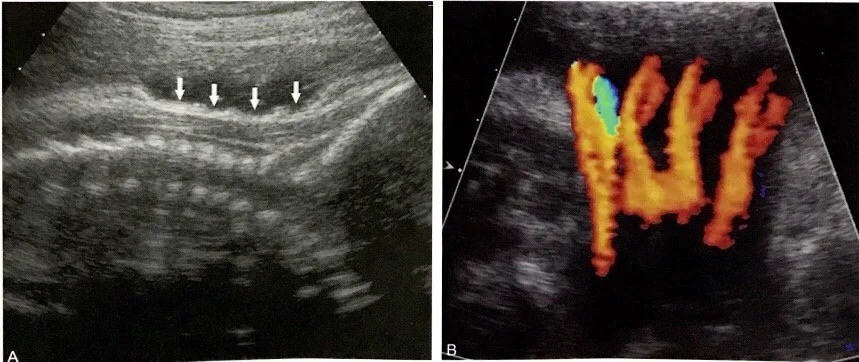

1、“U”型或“W”型压切迹,代表绕颈一周或二周。

绕颈4圈!